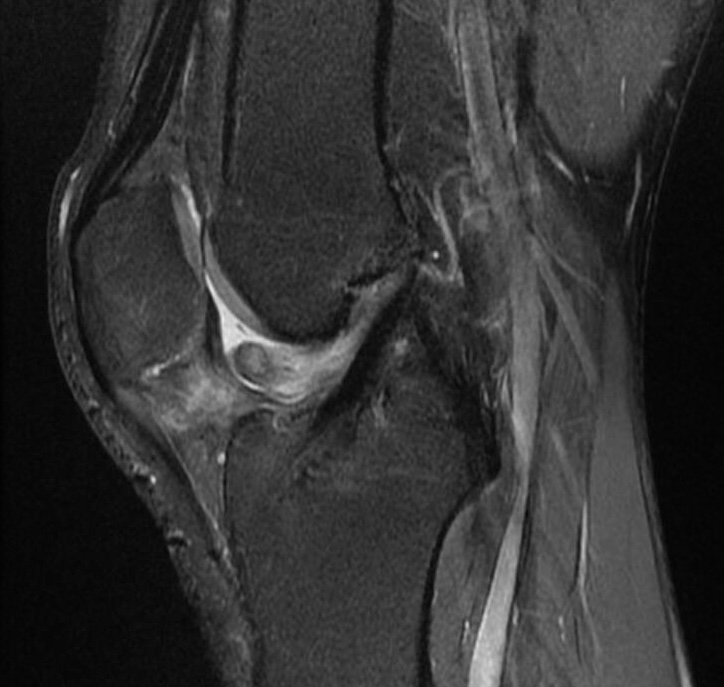

Pediatric anterior cruciate ligament tears and associated lesions Heat For Acl Tear An anterior cruciate ligament injury occurs if this ligament is a torn. The anterior cruciate ligament or ‘acl’ is a ligament inside the knee joint that provides stability to the knee. Anterior cruciate ligament injury is typified by a sudden, painful, audible pop noise. However, in grade ii or iii. A partially torn acl typically recovers after at least three. Heat For Acl Tear.